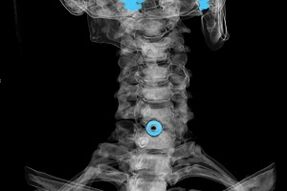

Діагноз встановлюють на підставі характерних симптомів, а також за допомогою:

- рентгенівські промені. Метод малоефективний, особливо на останніх стадіях розвитку остеохондрозу.

- МРТ (магнітно-резонансна томографія) шийного відділу хребта. Метод, що дозволяє побачити кісткові структури, грижі міжхребцевих дисків, їх розмір і напрямок розвитку.

- Комп'ютерна томографія. Менш ефективне рішення, ніж МРТ, оскільки важко визначити наявність і розмір грижі.